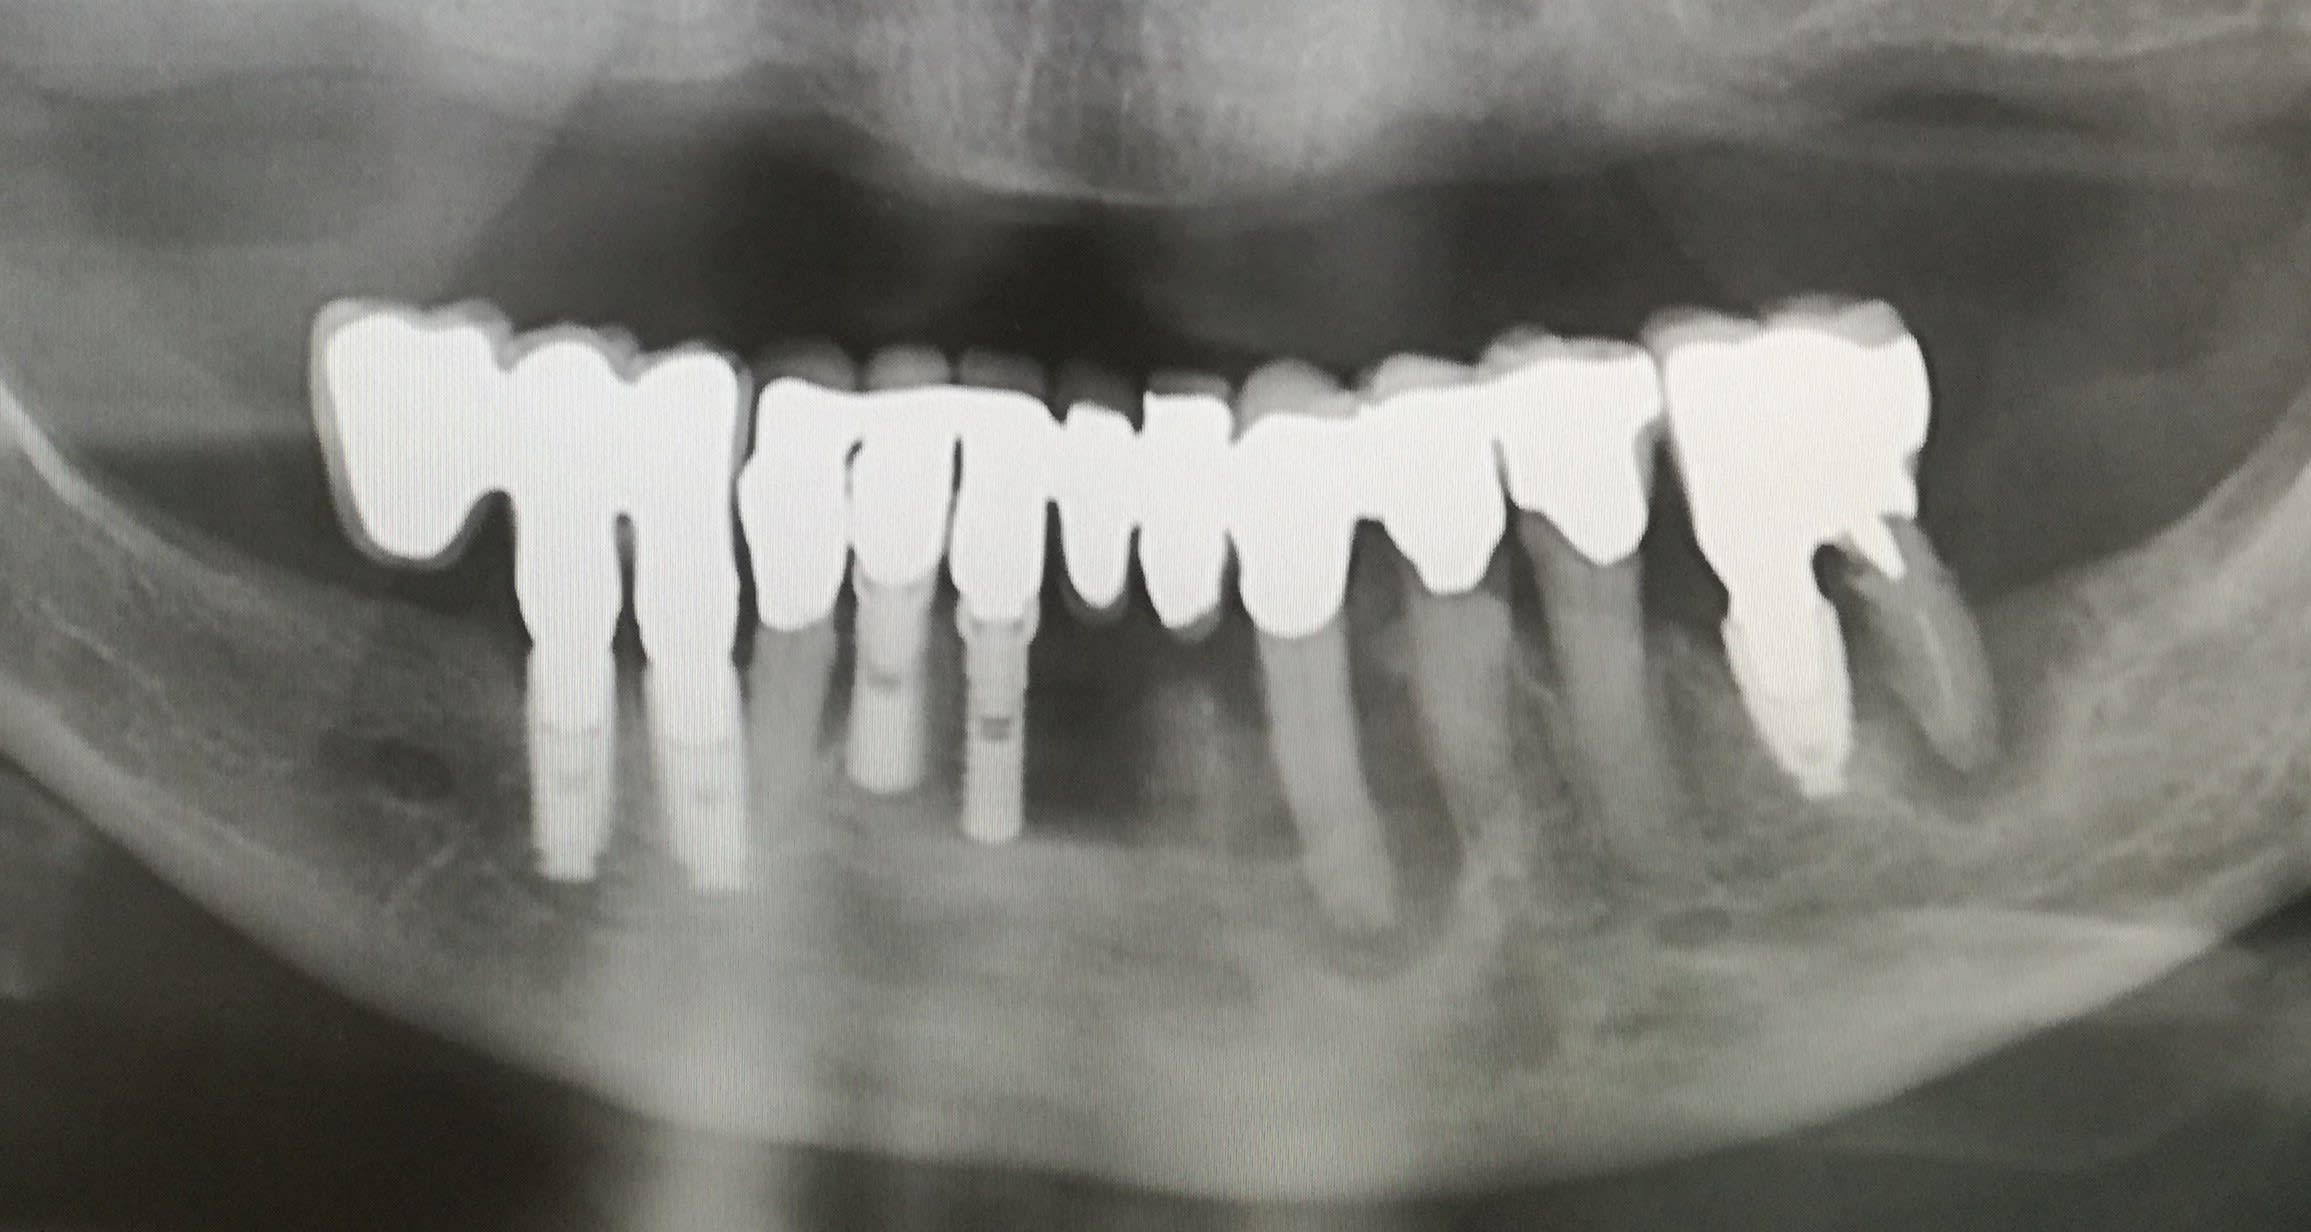

Faut reconnaitre que la dépose des implants s'est faite proprement, enfin d'après la radiographie.

Ça aurait pu être un carnage osseux.

Il a un drôle d’aspect le condyle droit. Ça donne quoi la palpation musculaire, notamment du Pterigoydien lat D ?

Je souhaitais faire la remarque que les soins initiaux avec toutes ces couronnes sur dents vivantes me rappelaient les traitements typique de pas mal de patients turques que j'ai pu croiser.

suis d accord avec toi , bien sur , et ce qui m étonne aussi , ç est la disproportion entre la longueur des racines / a la taille des couronnes .

le tout combiné , serait ce une cl3 que l on aurait machiné et verouillé pour des raisons esthétiques ? possible .

PS: je n ai jamais vu d aussi belles radios panoramiques .

> PS: je n ai jamais vu d aussi belles radios panoramiques .

On a régulièrement un soucis au service de radio avec des panos qui sont illisibles au niveau Incisivo-Canin, celles là sont dans la moyenne haute je dirais (sauf pour la deuxième au Mx ) . Un jour je me pencherai dessus si j'ai envie d'aller embêter le service radio, en attendant j'ai déjà eu fort à faire pour retoucher les prescriptions (et on débat encore pour savoir si l'ibuprofène doit aller dans les antalgiques ou anti-inflammatoires!).